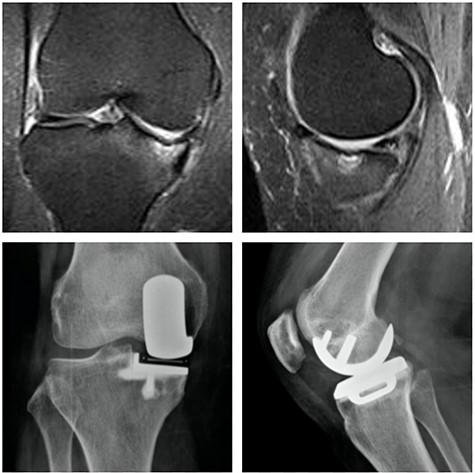

The implant used in our patients has a mobile bearing. Finite element analysis studies have already shown this prosthesis increases the tension forces just below the tibial component in the immediate postoperative period [11]. Thus, if the bone is not of good quality an early loosening could have a greater chance of occurring (author’s hypothesis). If the SIFK is very extensive, this bone may be compromised and cannot support this increased tension force. Our cases demonstrated this is a possible theory, because such failure did not occur in other cases without severe involvement of subchondral bone (Fig. 5). The use of mobile or fixed bearing implants could be a concern. However, literature shows no difference related to clinical outcomes, radiographic evaluation, revision rates and survivorship [13].

Top: coronal (left) and sagittal (right) T2 MRI with MP SIFK and a mild articular irregularity; Bottom: anterior (left) and lateral view (right) X-ray images 2 years after surgery with good clinical and functional results.